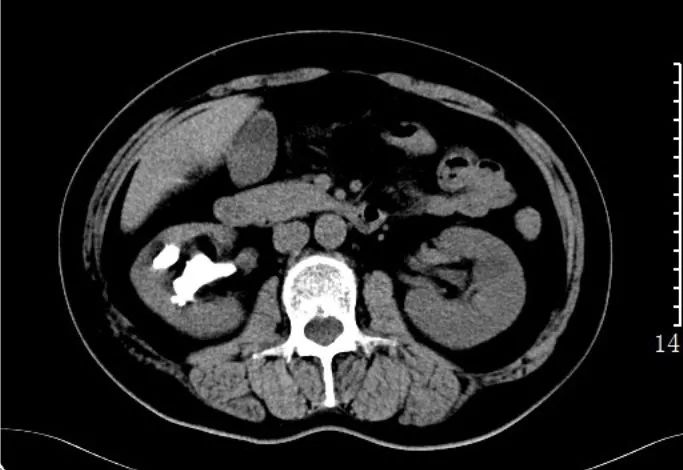

肾结石:CT平扫,右肾见不规则鹿角状高密度影,为铸型结石。

输尿管结石:CT平扫,左肾及左输尿管扩张积水,下段输尿管内可见小结节状高密度影。另见右肾小结石。